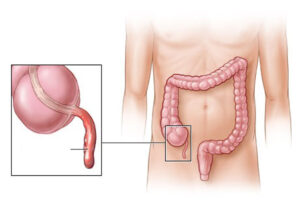

ما هي استئصال الزائدة الدودية بالمنظار عملية الزائدة الدودية بالمنظار (Laparoscopy appendectomy) هي إجراء طبي يتم من خلاله استئصال الزائدة الدودية المتصلة بالقولون في حال

سرطان المستقيم هو نوع من السرطان ينشأ على هيئة نمو للخلايا في المستقيم. ويوجد المستقيم في آخر الأمعاء الغليظة بطول عدة سنتيمترات. حيث يبدأ المستقيم

سرطان القولون هو نمو للخلايا يبدأ في جزء من الأمعاء الغليظة يسمى القولون. والقولون هو أول أقسام الأمعاء الغليظة وأطولها. أما الأمعاء الغليظة فهي الجزء